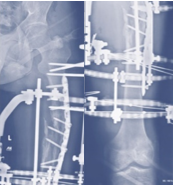

Case-V

53 years, male;

Comminuted fracture mid shaft of Radius & Ulna (Figure 18-21).

Figure 18 Pre-operative x-ray.

Figure 19 Follow up x-ray DCP fixation with infection.

Figure 20 X-ray after Ilizaro Osteo-synthesis.

Figure 21 X-ray after union.